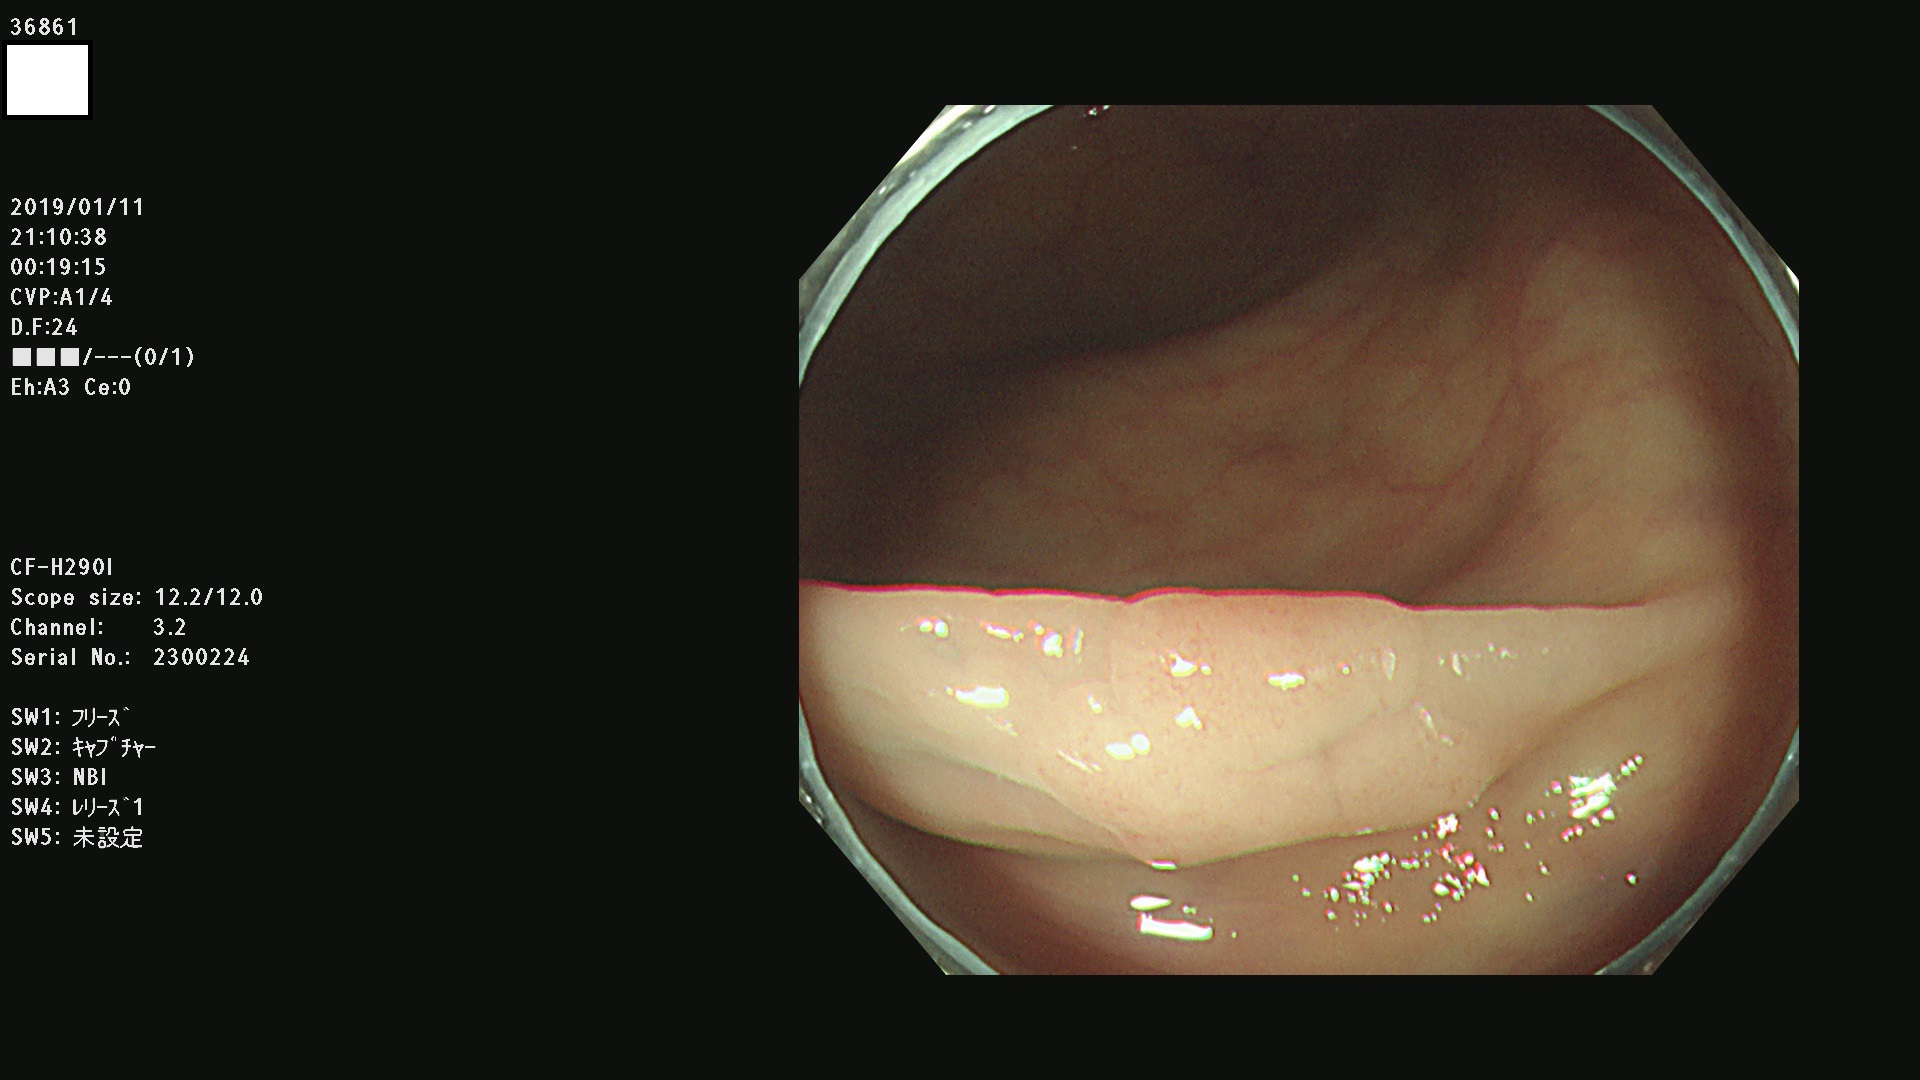

36804 36806 36807 36808 36809 36810 36811 36813 36815 36816 36817 36818 36820 36821 36822 36824 36825 36826 36828 36829 36830 36831 36832 36833 36834 36835 36837 36840 36841 36842 36845 36846 36848 36849 36851 36852 36853 36854 36855 36857 36859 36860 36861 36862(SSAPのみ) 36863 36864 36866 36868 36869 36870 36873 36875 36877 36878 36879 36881 36882 36883 36884 36885 36886 36887 36888 36889 36891 36892 36893 36894 36895 36896 36897 36898 36899

発見困難で危険性の高い平坦型病変(上記100名より抽出)